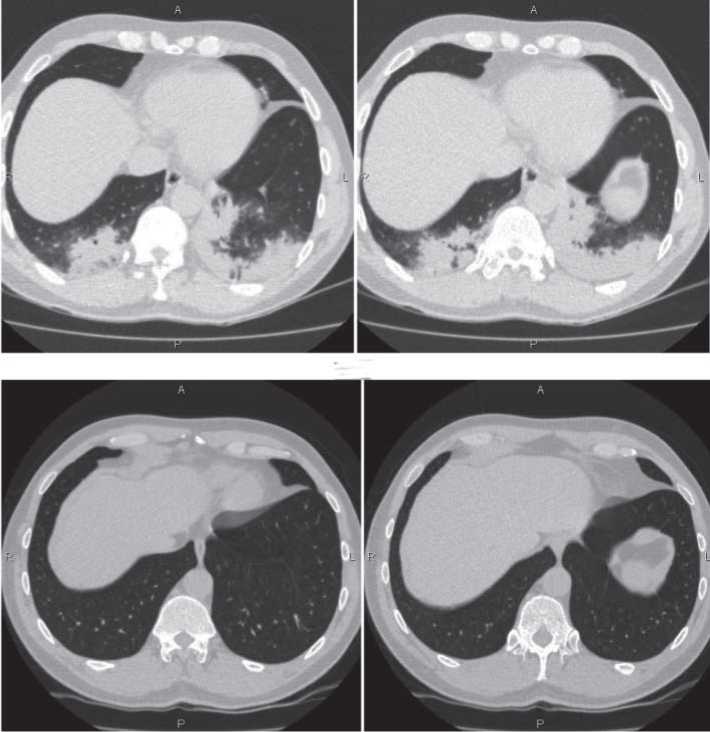

При контрольном обследовании через 6 месяцев после перенесенной пневмонии больной Д. жалоб не предъявлял. При объективном осмотре патологических изменений не выявлено. Анализ крови в норме. Спирометрические показатели не изменены: ЖЕЛ - 5,91 л (102%); ОФВ1 - 4,51 л (99%); ОФВ1/ЖЕЛ - 76%. Учитывая, что рентгенологические признаки легионеллезной пневмонии могут сохраняться до 6 месяцев [12], выполнена КТ легких, которая не выявила отклонений от нормы (рис. 2).

Рис. 2. Спиральная КТ груди больного Д. в динамике от 30.05.2016 г. (а) и 18.11.2016 г. (б).

Спиральная КТ груди от 30.05.2016 г.: в S10 сегменте правого легкого и S9 10 сегментах левого легкого на фоне диффузного уплотнения легочной паренхимы по типу «матового стекла» и утолщенных междольковых перегородок, переходящих в плевропульмональные спайки, участки плевропневмонической инфильтрации легочной ткани с наличием «воздушной бронхографии». Множественные очаговые уплотнения легочной ткани обоих легких: в паренхиме правого легкого - в S1 (1), размерами 3x3 мм, в S3 (2) - до 2x3 мм, в S5 (1) - 4x2 мм, в S4 (2), субплеврально - до 3x3 мм, S8 (1) - 3x3 мм; в паренхиме левого легкого в S1(1) - размерами 4 2 мм, S4 (1) - 5x3 мм, в S5 (1), субплеврально - 2x3 мм, S9 (1) - до 3x2 мм. В S6 правого легкого визуализируется единичная парасептальная булла, размерами 8x5 мм. В S5 левого легкого наблюдается участок уплотнения легочной ткани, с нечеткими, неровными контурами и наличием тяжей к прилежащей плевре, размерами 13x6 мм. Множественные плевропульмональные спайки, преимущественно в апикальных и базальных отделах обоих легких. Ход и проходимость трахеи, главных и долевых бронхов не нарушены, стенки их умеренно утолщены, с наличием единичных обызвествлений в стенках трахеи. В единичных лимфатических узлах правой подмышечной группы наблюдаются мелкие обызвествления. Заключение: плевропневмония в S10 сегменте правого легкого и S9 10 сегментах левого легкого. Множественные очаговые уплотнения обоих легких. Пневмофиброз в S5 левого легкого.